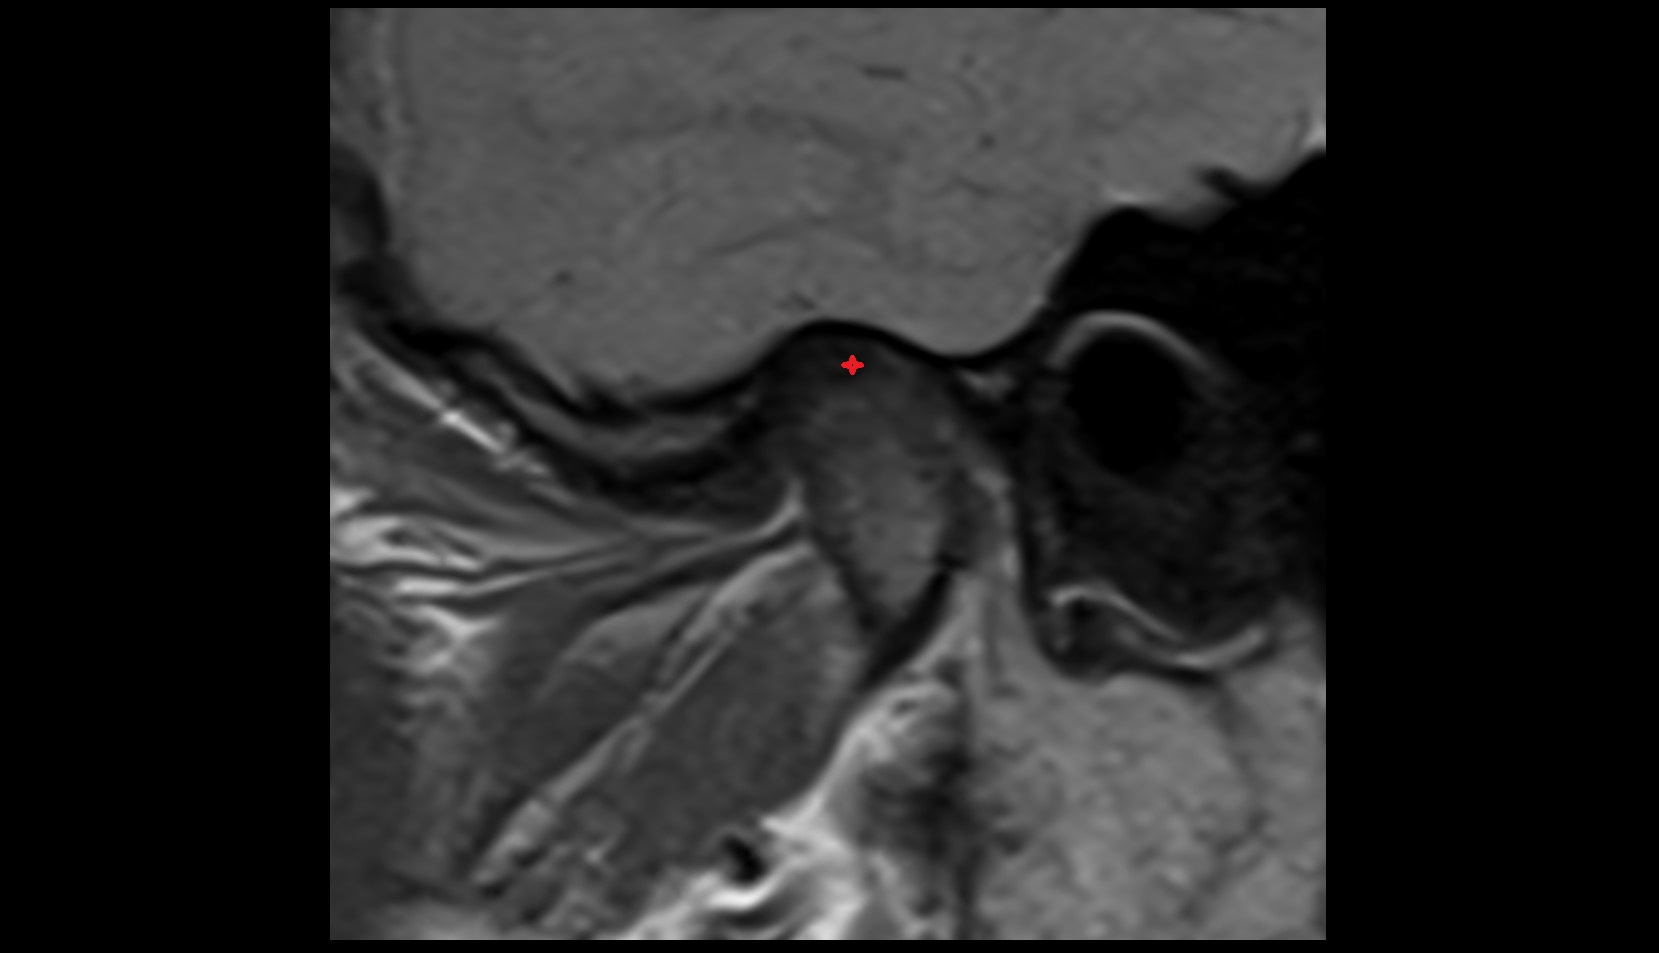

- Temporomandibular joint

- Articular disc of temporomandibular joint

- Articular eminence

- Mandibular condyle

- Mandibular fossa